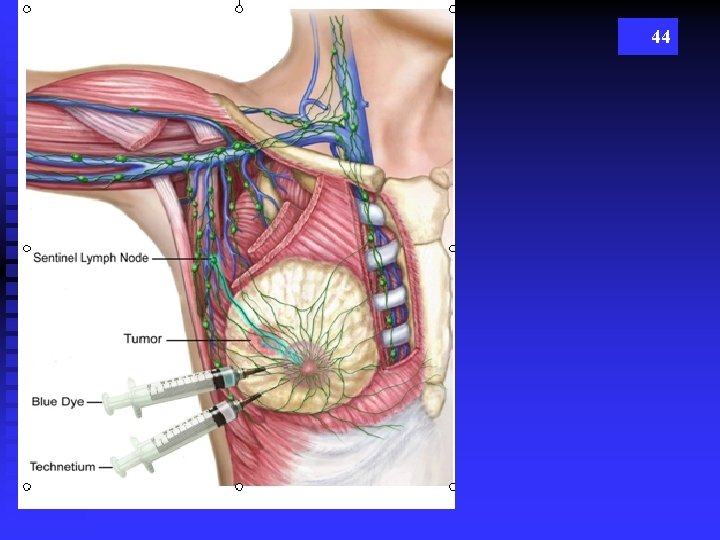

Lymph Nodes n Lymphatic vessels of the breast drain laterally and medially u Laterally into the axillary lymph nodes (C & D) t 75& drain toward axilla u Medially into the mammary lymph nodes t 25% toward mammary chain (F) 42

43 Breast Scintomotography Isotope matches tumor to node involvement More on Breast Pathology & Procedures next lecture…. .